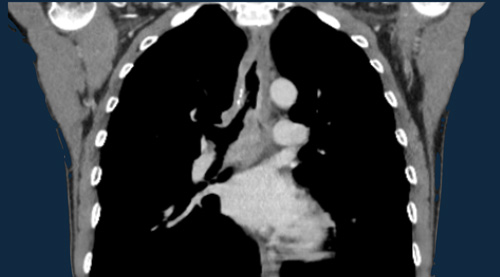

Pulmonary Hypertension and Thromboembolic disease

Pulmonary Hypertension